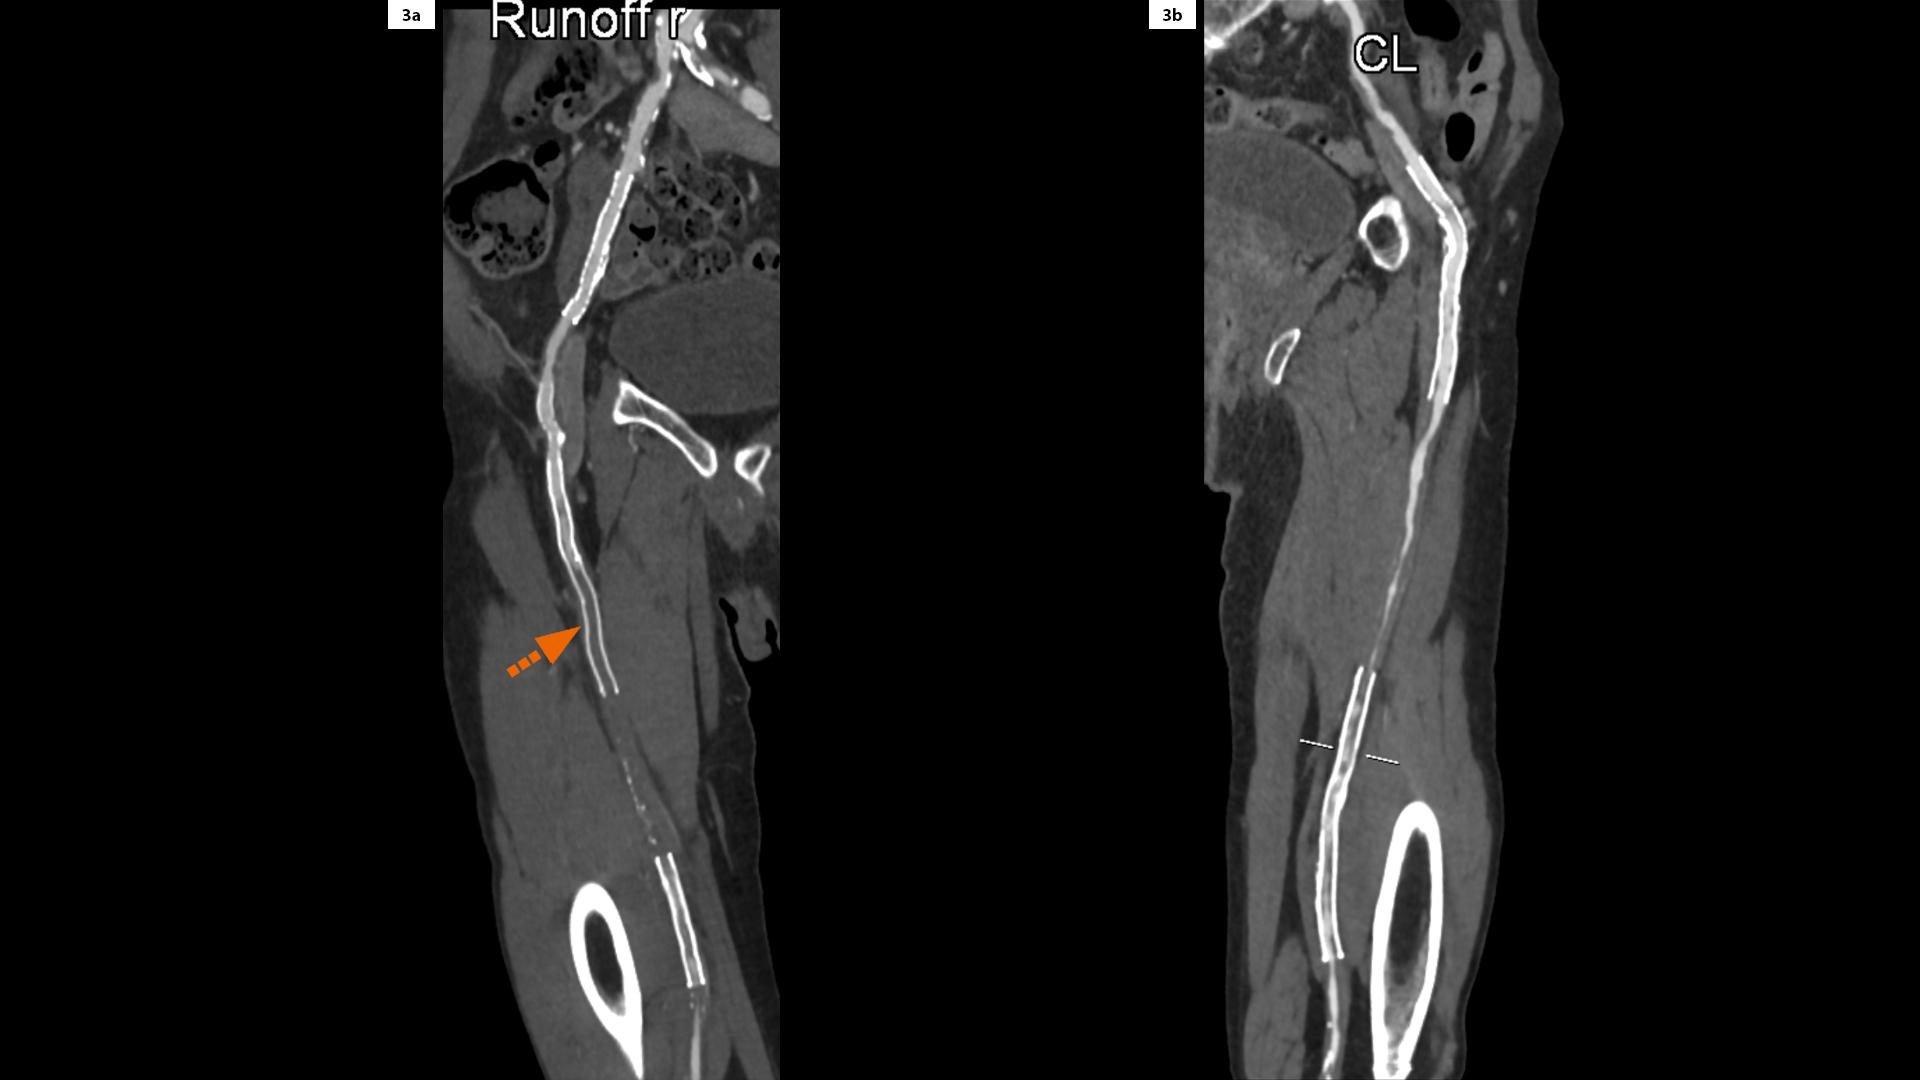

From www.jvscit.org

Offlabel use of interwoven carotid stent in common femoral artery occlusion after surgery What Is Stent Occlusion stent thrombosis is a blood clot that forms in a coronary stent following percutaneous coronary intervention (pci). stent thrombosis, also known as abrupt vessel closure, occurs when an implanted coronary stent causes a. It can cause shortness of breath. The gradual renarrowing of the area inside the stent, known as restenosis, and the. stent thrombosis is a. What Is Stent Occlusion.

A Sixmonth CTA followup shows stent occlusion (arrow). B Sixmonth... Download Scientific What Is Stent Occlusion stent thrombosis, also known as abrupt vessel closure, occurs when an implanted coronary stent causes a. two main complications can occur with coronary stents: stent thrombosis is a devastating complication of stent implantation, and strict attention to patient risk factors and ability to. coronary artery occlusion is a partial or total blockage of one of the. What Is Stent Occlusion.